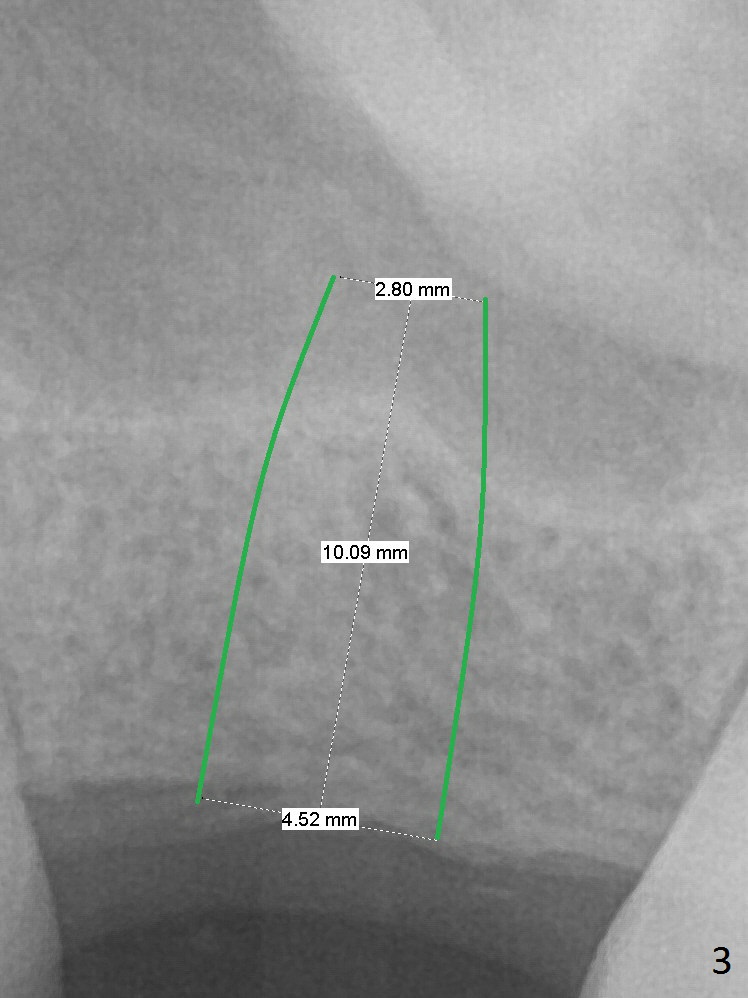

Place Implant Between Two Layers of Sinus Floor

A 47-year-old man agrees implant at #14 (Fig.1). He worries about the bone height. There appear to be 2 layers of the sinus floor (Fig.1,2 (arrowheads: upper one)). The horizontal plate of the palate is indicated by *. An IBS implant will be placed between the 2 layers of the sinus floor as shown in Fig.3. Osteotomy is initiated with Magic Split, followed by Magic Expanders (initial depth 9 mm gingival level) or Magic Lifter. Before placing the implant, insert PRF and Allograft with a condenser with a stopper.